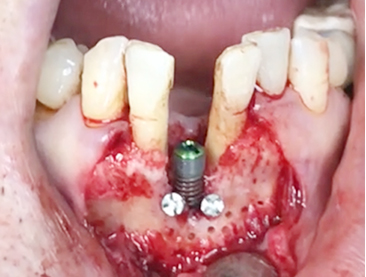

Implants/Bone Grafting

Simultaneous bone graft and implant placement